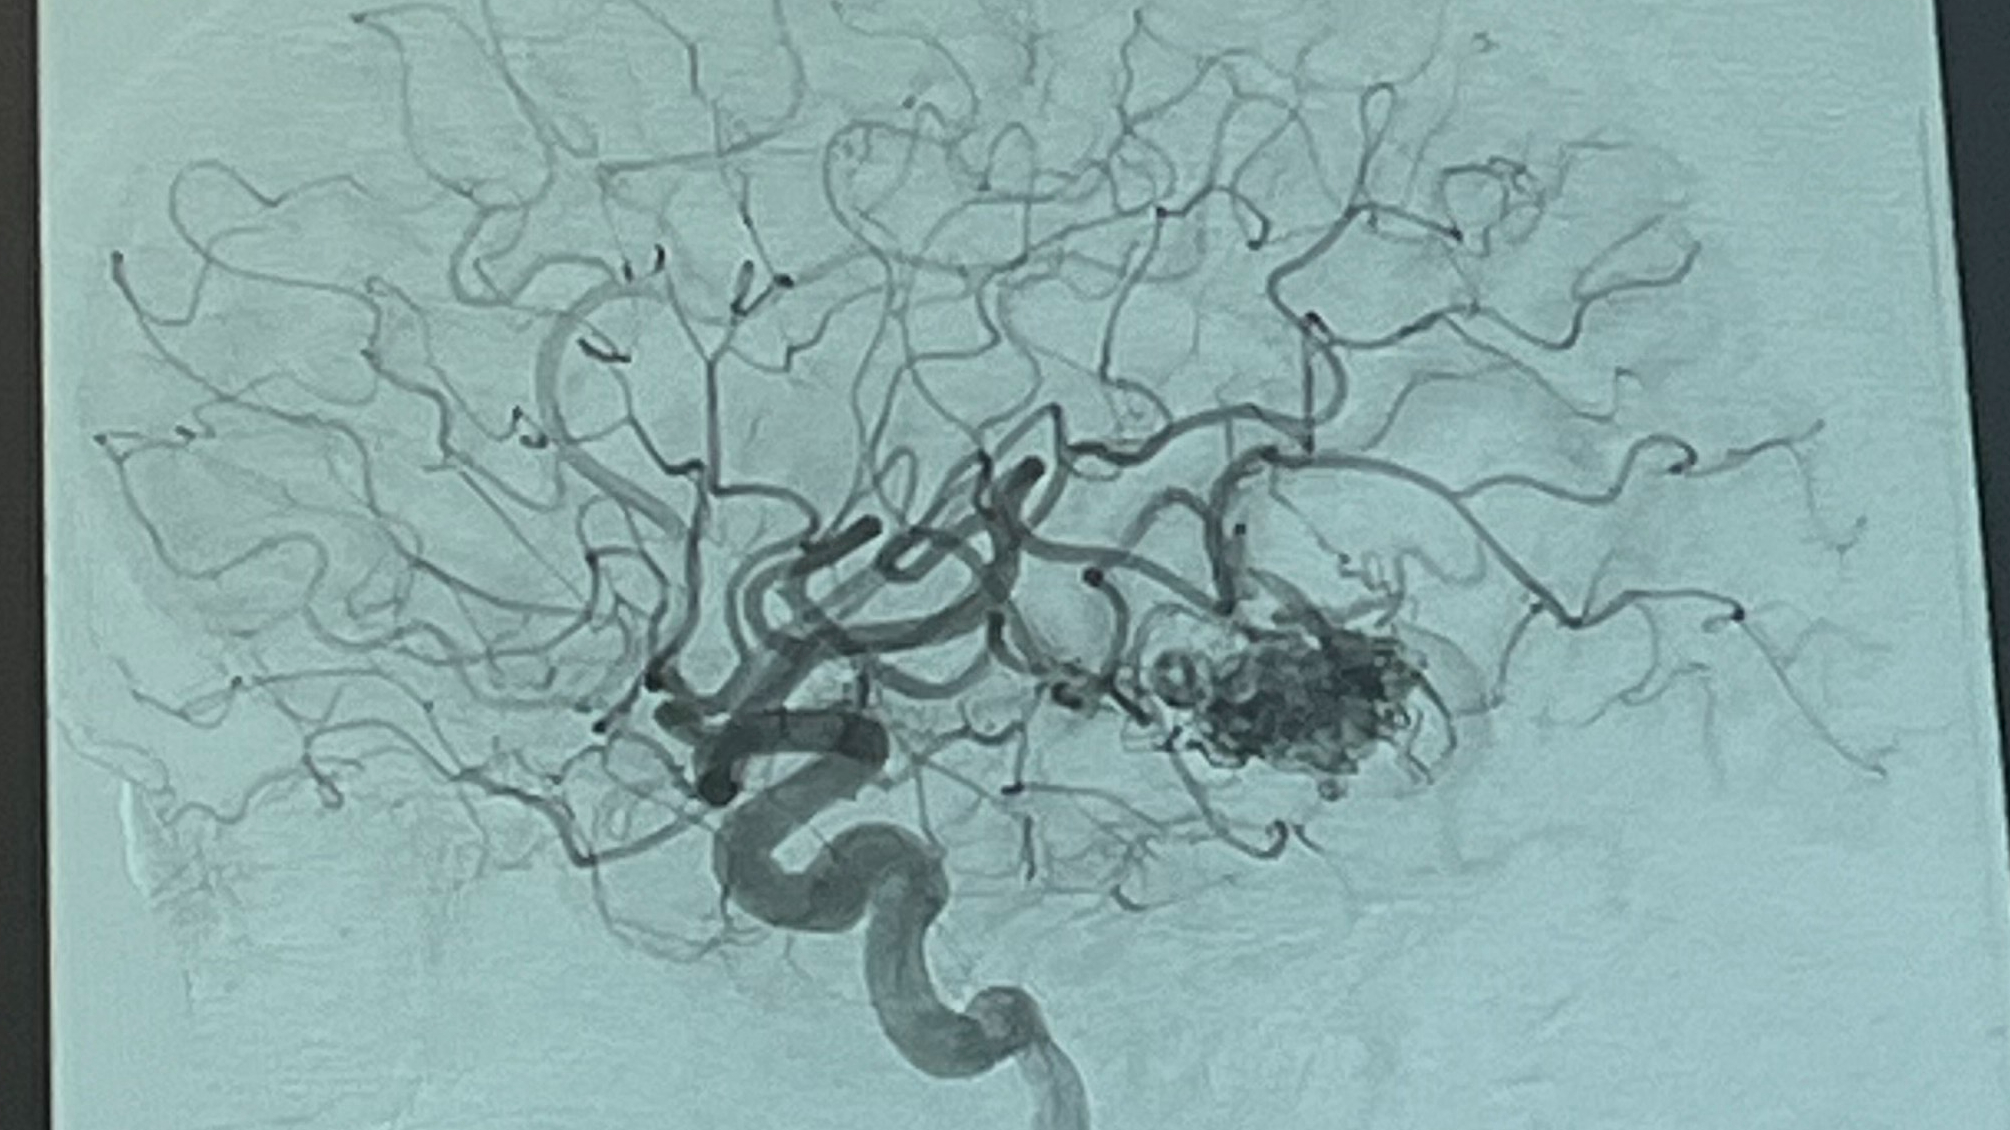

Emry's AVMersary Fundraiser!